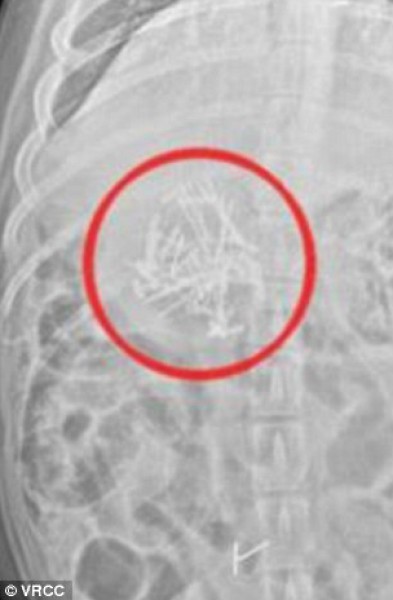

حيث قامت بالتهام البركان الصناعي وهو عبارة عن مشروع الفتاة بايتون "13 عام" الخاص بمادة العلوم والذي قامت بتصنيعه من قطع الحلوة وحبات شوكولاته M & M حيث قامت بلصق القطع ببعضها البعض بواسطة دبابيس صغيرة .

وتم نقل الكلبة إلى المشفى وتم إزالة أكثر من 50 دبوس معدني من عمدتها.